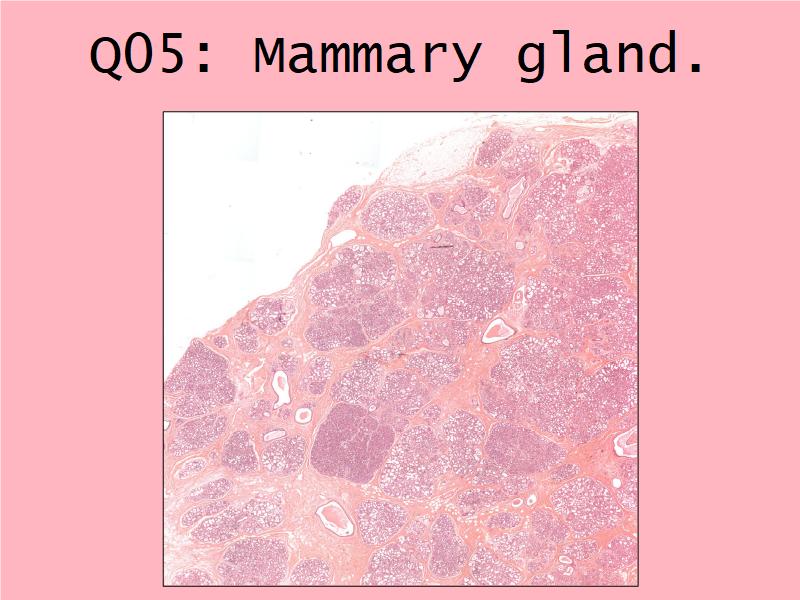

Slides

- Mammary gland - slide 57

- Nipple - slide 15

Mammary gland

Write short notes describing the structure of the mammary gland.

(5)

Mammary gland

- Compound tubuloalveolar gland

- 12 - 20 glands

- Each with own lactiferous duct

- Each with own lactiferous sinus

- Opens on skin at apex of nipple

Two stages

- Resting

- Active

Resting and active

Describe the resting mammary gland and compare with the active gland.

(8)

Resting gland

- Connective tissue dominate

- More adipose tissue

- Glandular tissue reduced

Active gland

- Terminal ducts expand

- Forms alveoli

- Connective tissue reduced

- Adipose tissue reduced

- Glandular tissue dominate